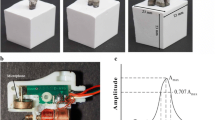

QPD involves lightly percussing the tooth while recording and analyzing the force-time response of the specimen. As opposed to cyclic loading, percussion loading only occurs during the few tenths of a millisecond that the percussion rod is in contact with the tooth. During that period, the QPD percussion rod administers a reproducible level of kinetic energy to the tooth that is governed by the rod’s mass and initial velocity prior to impact. Thus, consistent initial kinetic energy is the controlled test condition by which measured mechanical responses to the resulting percussion are compared using QPD.

The solid models of these teeth were meshed for finite element analysis (FEA) in MSC Apex. The pre-processing, processing and post-processing steps were performed in MSC Marc/Mentat software. The finite element mesh that we developed for modeling a mandibular second molar is illustrated in Fig. 2. A percussion rod was also included in the present 3D models to simulate QPD accurately and for predicting the force measured by a sensor in the rod as a function of time. The present FEA meshes have a total number of about one million elements each. The location and angle of the percussion rod to each tooth was based on typical clinical use of the Periometer hand piece. For molars, the rod percussion is generally positioned at the buccal-mesial cusp since this is the easiest cusp on these teeth to access. This rationale was also used to apply similar percussion rod positioning for in vivo studies conducted previously [26,27,28,29].

The percussion rod was free to move in only its axial direction with a mass of 9 g and an initial velocity of approximately 60 mm/s, which are consistent with the operation of the Periometer hand piece [31]. The models were run with a time increment of 2 µs. A direct integration method was used to obtain the solution to the equations of motion for our models.